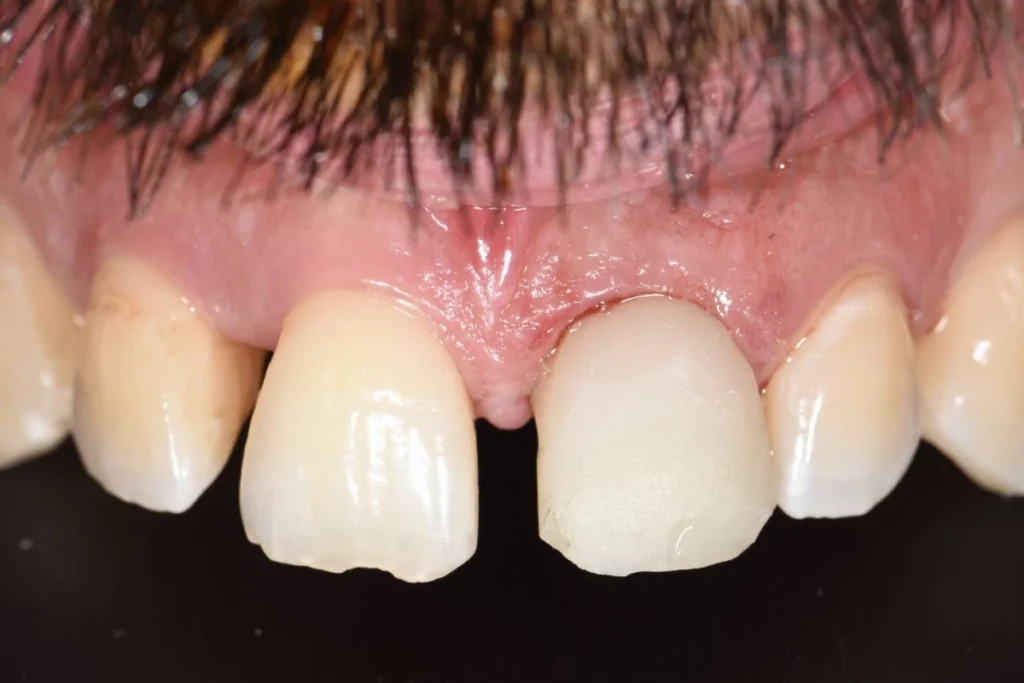

Mr M., 33 ans, se présente à la consultation suite à un traumatisme survenu à la boxe. La facette dentaire réalisée il y a plusieurs années par un confrère a été perdue après un coup encaissé au visage.

Le patient souhaite remplacer sa prothèse pour pallier au préjudice esthétique en urgence. Malheureusement, la dent présente une carie qui ne permet plus de conserver cette dent. Une dent provisoire est réalisée au cabinet afin de gérer l’urgence esthétique évidente et de permettre au patient de réfléchir aux soins proposés « à tête reposée » 🙂

Après un traitement parodontal initial nous permettant de mettre l’environnement buccal dans les meilleures conditions pour l’intervention, nous décidons avec le patient de planifier la chirurgie. Un protocole d’extraction implantation et mise en esthétique immédiate est décidé afin d’éviter au patient le port d’une prothèse amovible.

Le patient repart du cabinet avec une couronne fixée à l’implant tout juste mis en place! En contre partie, le patient devra faire l’effort de ne pas solliciter sa dent lors des repas afin de laisser l’implant s’ostéo intégrer (se souder) à l’os.

L’intervention est réalisée sous anesthésie locale et doit être complètement indolore. Le patient est revu 3 mois après l’intervention pour prendre une empreinte. Le patient est invité à se rendre au laboratoire de prothèse situé dans le 17ème afin de discuter de la forme de la dent avec l’artisan céramiste. Dans le cas présent, il souhaitait conserver l’écart existant entre ces incisives afin de conserver l’identité de son sourire.

Lors de cet entretien, le prothésiste enregistre également toutes les données de teinte et d’état de surface des dents adjacentes afin de faire la parfaite illusion d’une dent naturelle.

Environ une semaine après la prise de l’empreinte, un essayage est réalisé au cabinet. Si tous les paramètres esthétiques et fonctionnels sont validés, la couronne est posée dans la foulée.

Il est parfois nécessaire de prendre le temps d’une retouche au laboratoire afin d’obtenir le rendu escompté.